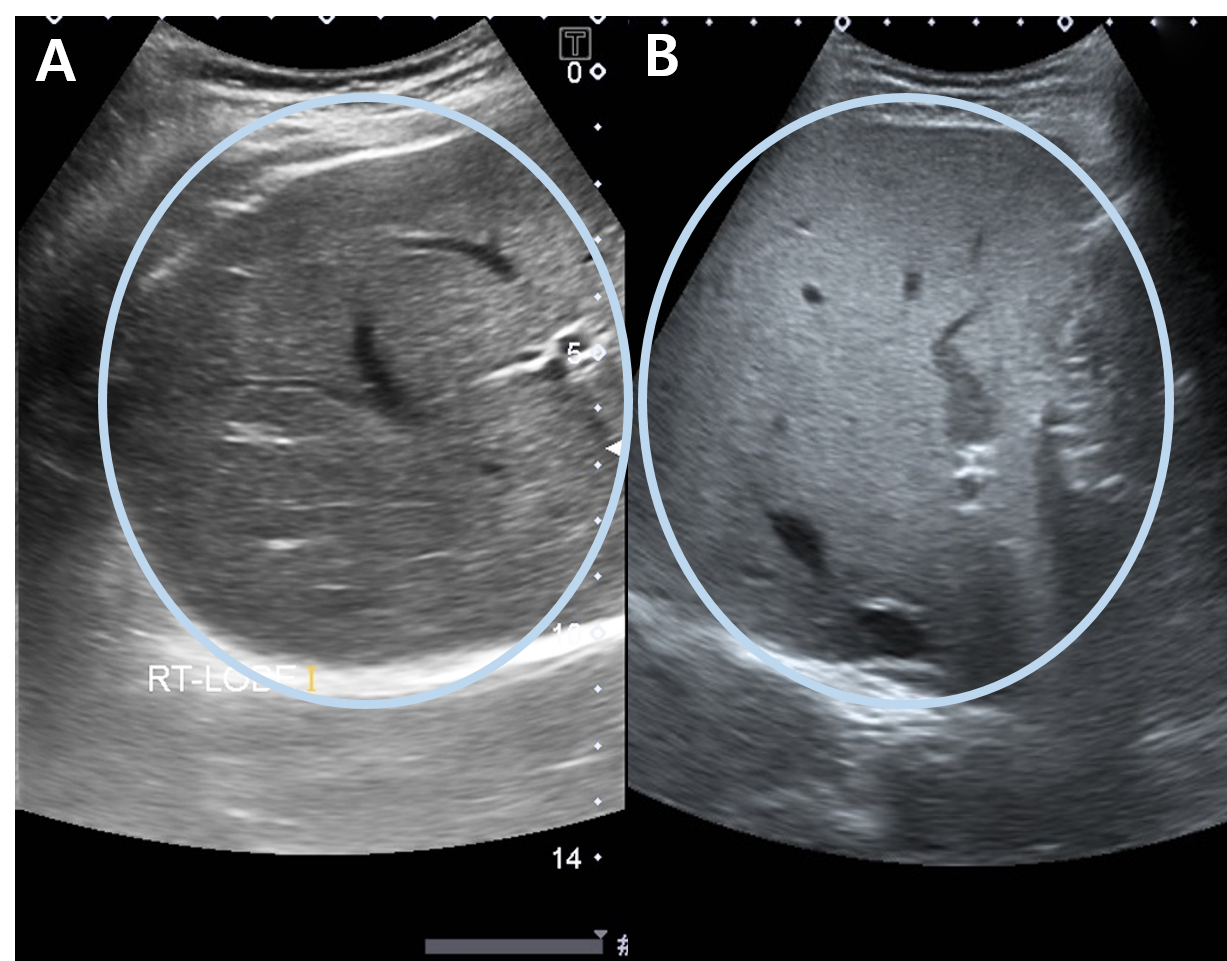

▶ 정상 간 (A)과 지방간(B)의 초음파 영상. 간은 하늘색 동그라미로 표시하였다. 지방간(B)이 정상 간(A)에 비해 조금 더 하얗다(고에코성).

지방간 진단에 가장 쉬운 검사는 복부 초음파입니다. 복부 초음파에서는 간을 항상 검사하므로 지방간을 쉽게 알 수 있습니다. 초음파 검사는 방사선이 없고 간편하게 검사가 가능하며, 가벼운 지방간도 진단 가능합니다. 하지만 초음파를 시행하는 의사에 따라 영상을 주관적으로 판단하기 때문에 진단에 차이가 있을 수 있습니다.